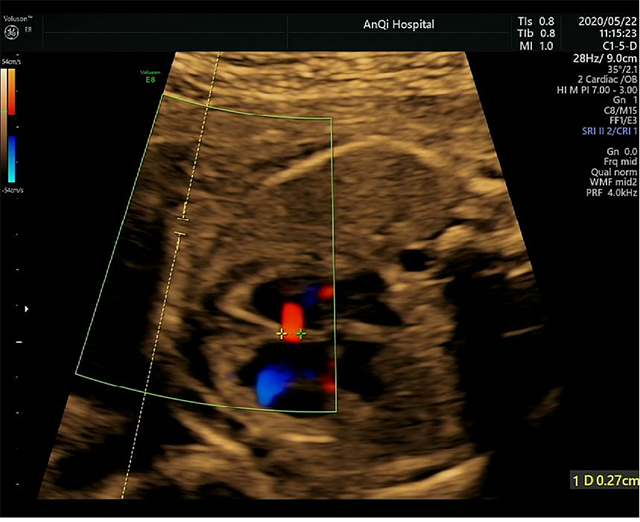

上图为我院筛查出的异常病例,超声显示:胎儿右心系统明显增大,左右心比值不对称,室间隔可见回声失落、主动脉及峡部内径稍细。因孕妇未做过四维,检查时已超过33周。

该孕妇得知北京安贞医院耿斌教授定期到安琪会诊后,立即进行了预约,后经耿斌教授会诊后,考虑胎儿左右心比例严重失调(卵圆孔近闭合所致),室间隔缺损(膜周)。

【专家建议】唯恐胎儿卵圆孔过早闭合,所以晚孕期要增加产检次数及时关注,条件准许的情况下尽可能提前采取措施生产,减少宝宝临产期在孕妇肚子里的时间、降低胎儿危险的机率。